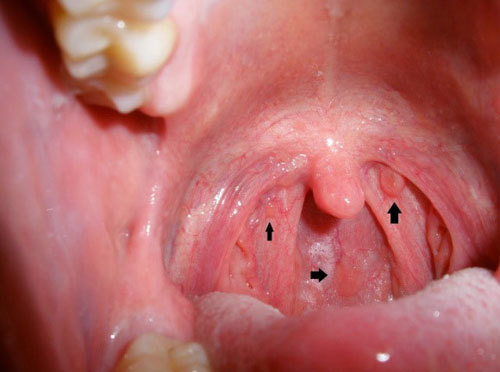

Triệu chứng bệnh ung thư vòm họng

Ung thư vòm họng là loại u ác tính thường gặp, khó phát hiện sớm do các dấu hiệu dễ nhầm lẫn với những loại bệnh thông thường.

Ung thư vòm họng là loại u ác tính thường gặp, tốc độ phát triển của bệnh cũng tăng tương đối nhanh, phổ biến, rất khó phát hiện sớm do các dấu hiệu dễ nhầm lẫn với bệnh thông thường.